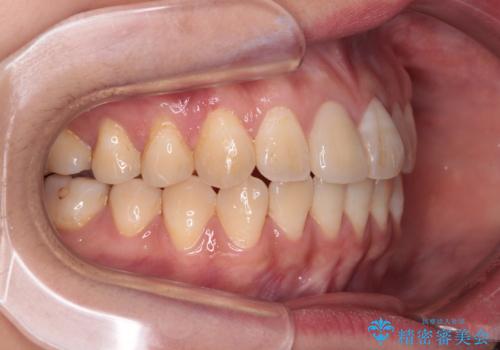

舌の突出癖による開咬と前歯の突出 インビザライン矯正治療

- 上下前歯の非接触と叢生を気にして来院された患者様です。

開咬の改善はインビザラインの最も得意とするところであるため、インビザラインを用いて矯正治療を行うこととしました。

治療開始直後に上顎前歯に激しい痛みが発現し、矯正治療を休んだり、マウスピースの装着時間を短くしたりと工夫をしましたが、残念ながら治療途中で失活していることが分かりました。

矯正治療の途中で前歯の根管治療とオールセラミッククラウンによる補綴治療を行い、その後インビザライン1セットを用いて細かい部分を仕上げました。